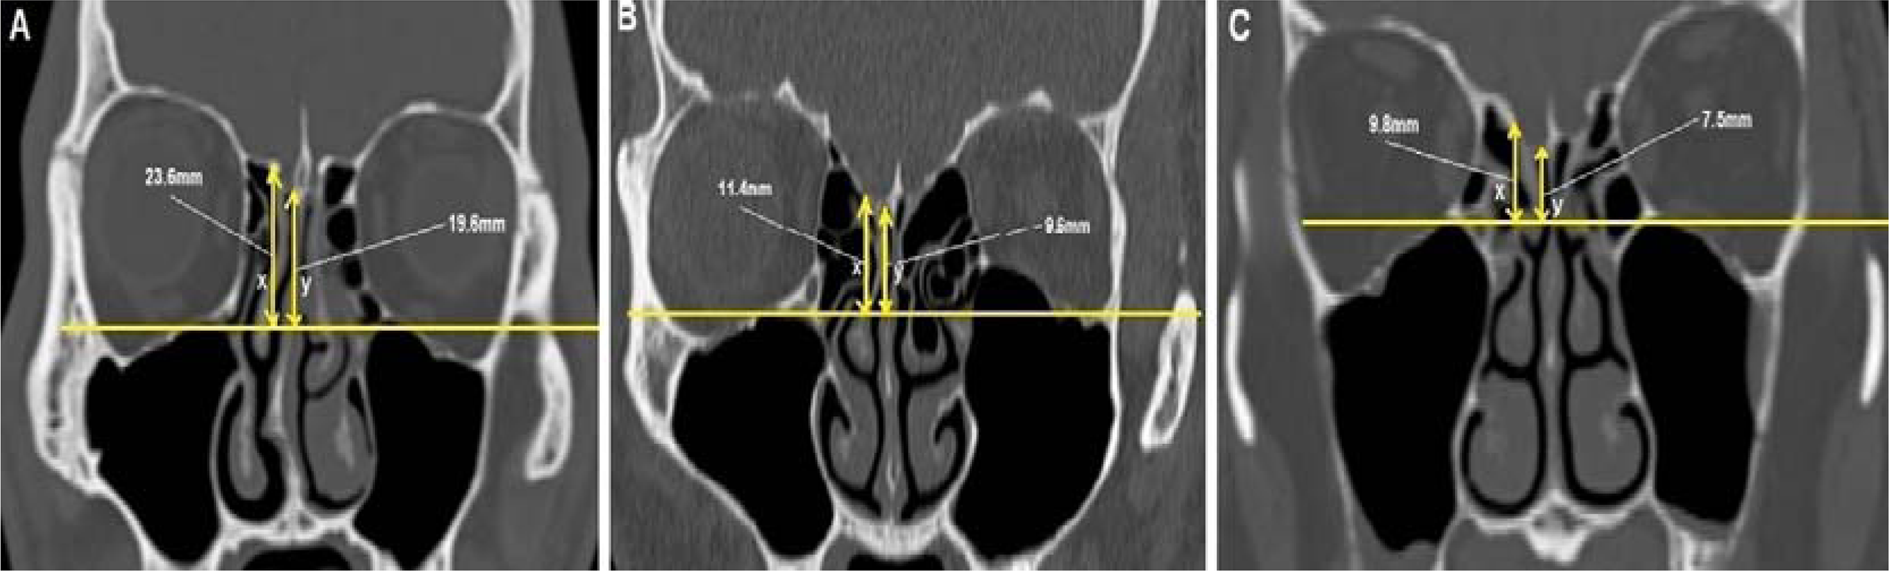

Figure 2

CT PNS coronal section showing the three types of TMS classification; (A) is Type 1 (low risk) where both OF-CP and OF-ER are 10 mm and above, (B) is Type 2 (moderate risk) where either OF-CP or OF-ER is less than 10 mm and (C) is type 3 (high risk) where both OF-CP and OF-ER are less than 10 mm.